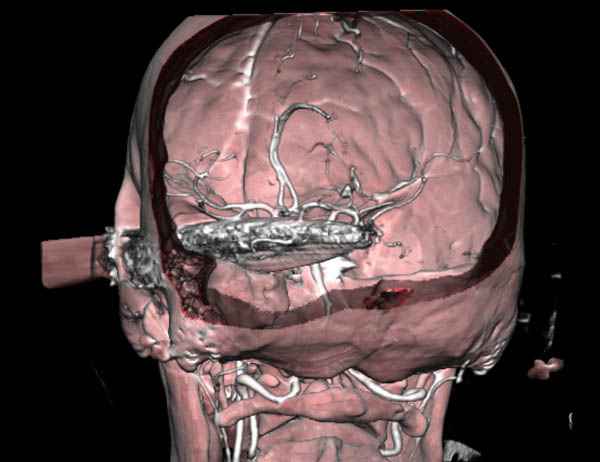

По протоколу сделаны все необходимые исследования: рентген, ангиограмма с 3Д реконструкцией, где обнаружили что все жизненно важные сосуды не задеты, даже некоторые "сидят" изгибаясь на ноже.